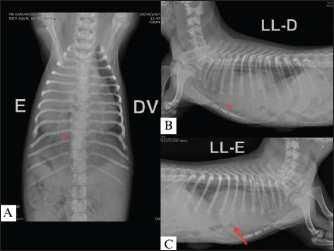

Shortly after the second visit, the patient was referred for emergency care due to cyanosis, expiratory dyspnea, and mild tachycardia. Furosemide (Teuto, Anápolis, GO, Brazil) was administered intravenously (IV) at a dose of 2 mg/kg along with fluid therapy (3 ml/kg/hour). In addition, the patient was hospitalized for monitoring respiratory pattern and vital parameters. Once the condition had stabilized, a new echocardiogram was performed with a microbubble test, which was negative and confirmed the diagnosis of VSD (Fig. 2). During the examination, the patient presented with a second episode of cyanosis and expiratory dyspnea, followed by respiratory arrest while in the lateral decubitus position. Consequently, left lateral, right lateral, and dorsoventral survey X-rays of the thoracic region were obtained, which indicated PPH (Fig. 3).

Fig. 3. Dorsoventral radiograph (A); right lateral (B) and left lateral (C) radiographs showing a markedly enlarged cardiac silhouette with a rounded shape and convex projection of the caudal portion (arrow), a sign of the ventral diaphragmatic silhouette, dorsal deviation of the trachea, and the presence of a tubular structure (*), containing gas and extending beyond the diaphragmatic silhouette, most clearly seen in (C), consistent with features suggestive of a peritoneopericardial diaphragmatic hernia. L, left; DV, dorsoventral; LL-D, right laterolateral; LL-E, left laterolateral.

Although VSD was first diagnosed because of the auscultation of a heart murmur and was associated in this case with PPH, these malformations are not always observed together. The clinical signs of respiratory distress present in the patient can be explained by the presence of abdominal organs in the chest cavity, rather than the hemodynamic alterations present in VSD. Hence, there was no reason to believe that the heart condition was cyanotic. The HPP was diagnosed by thoracic radiography, which revealed the presence of abdominal organs in the thoracic region as well as suggestive findings of diaphragmatic discontinuation.